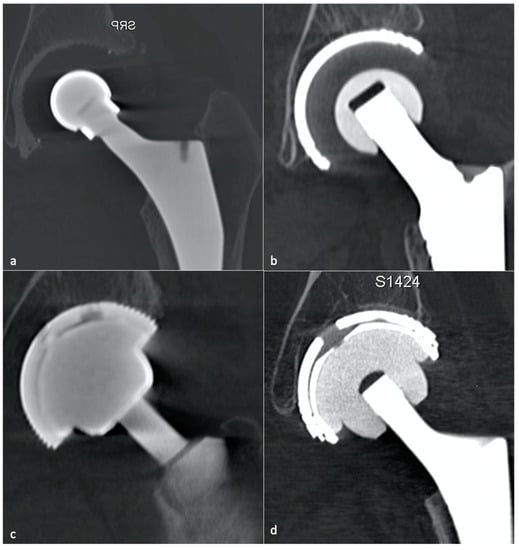

2.3. Bearing Surfaces